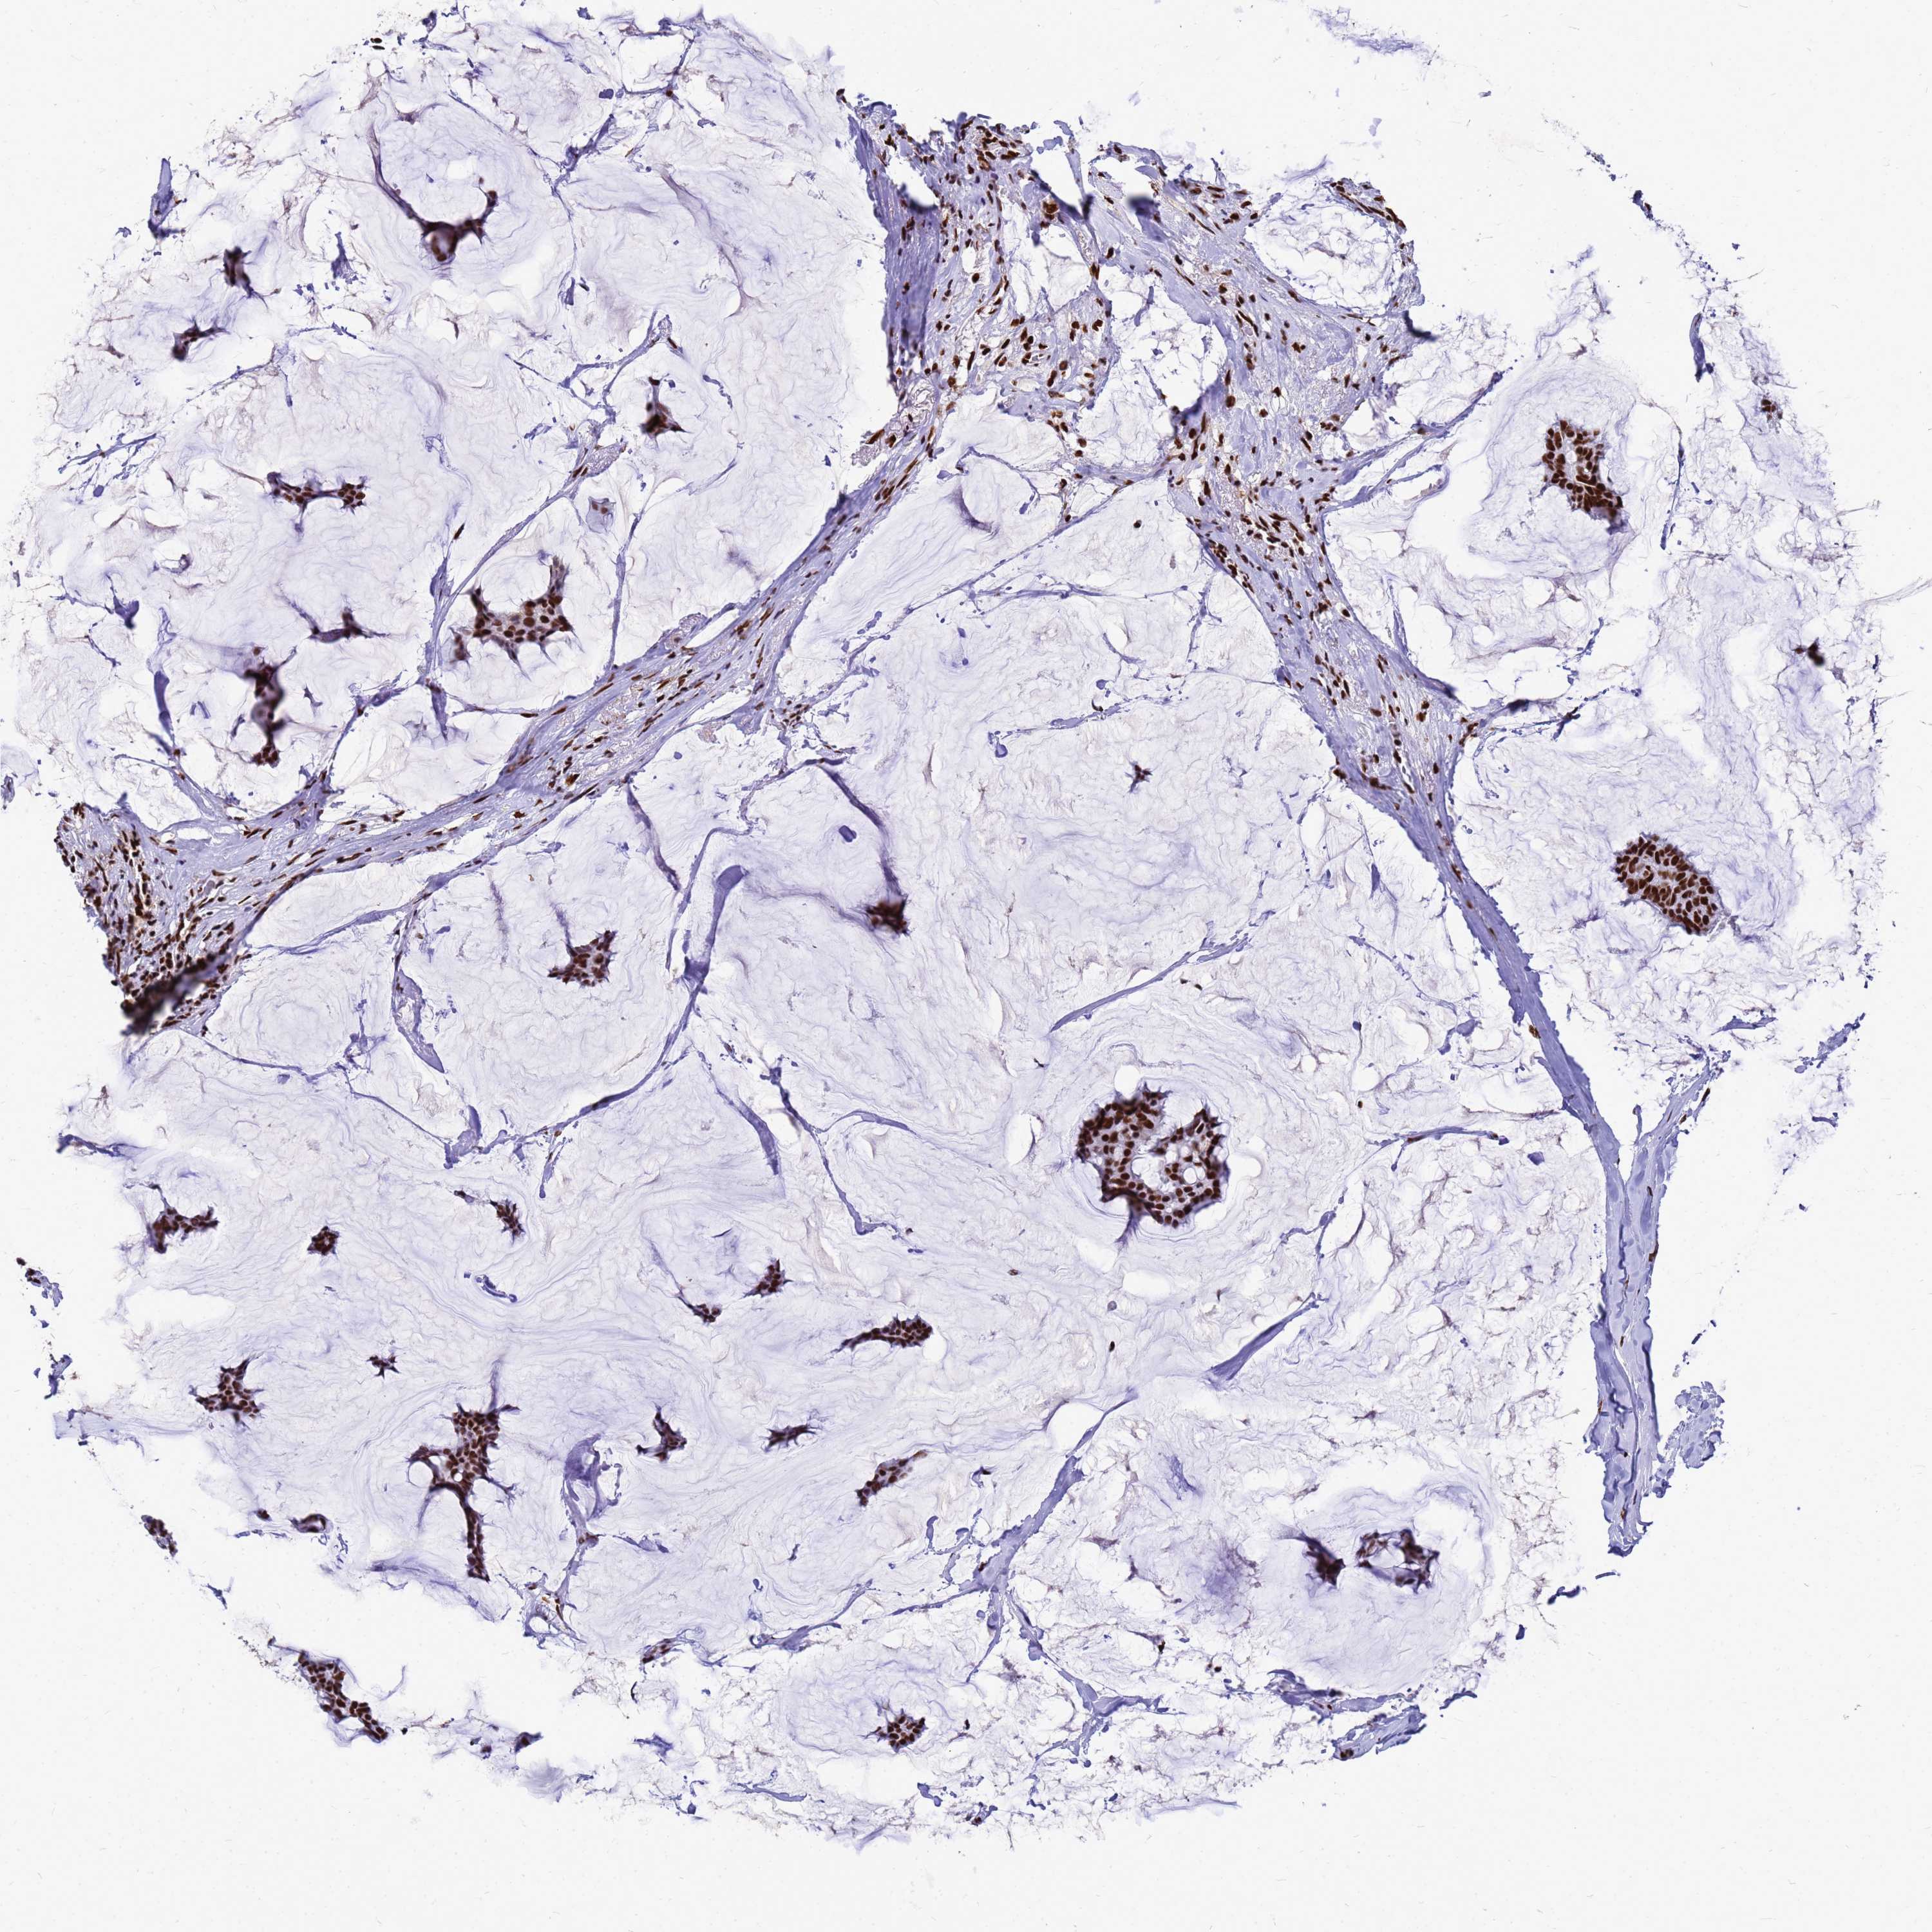

CANCER BREAST CANCER Show tissue menu

BRCA TCGA BRCA VALIDATION PROTEIN EXPRESSION

Breast cancer

Human cancer